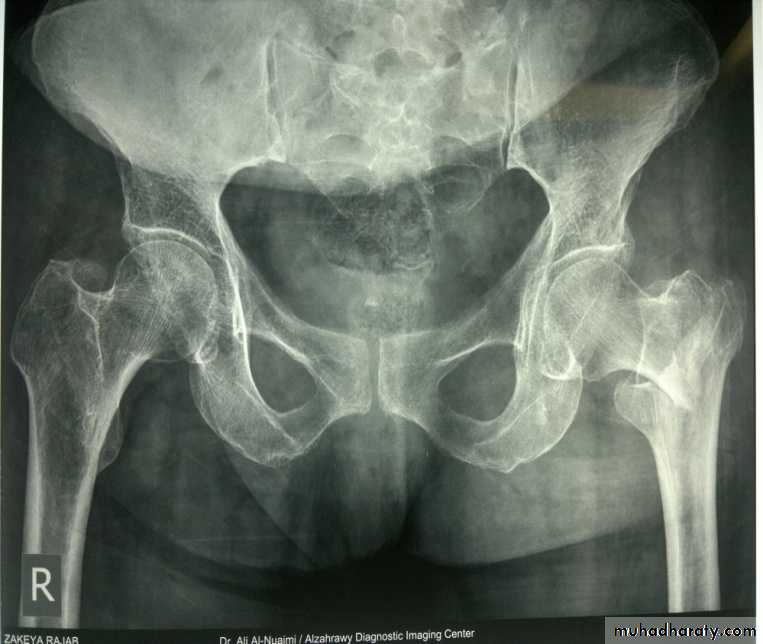

3- osteoarthritis of the hip joint .

Avascular necrosis of the femoral head will lead to osteoarthritis later on .The treatment is by total hip replacement .